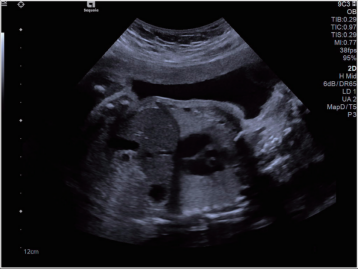

超聲圖像舉例

超聲

原理:超聲的原理是用超聲波穿透人體,當(dāng)聲波遇到人體組織時會產(chǎn)生反射波,通過計算反射波成像;

應(yīng)用:主要用于腹部、婦科、心臟等的檢查;

優(yōu)點:多方向觀察,實時成像;

缺點:超聲受氣體干擾大,對于腸道等含氣體較多的器官,超聲診斷準(zhǔn)確率會降低,所以一般腸道檢查使用腸鏡;